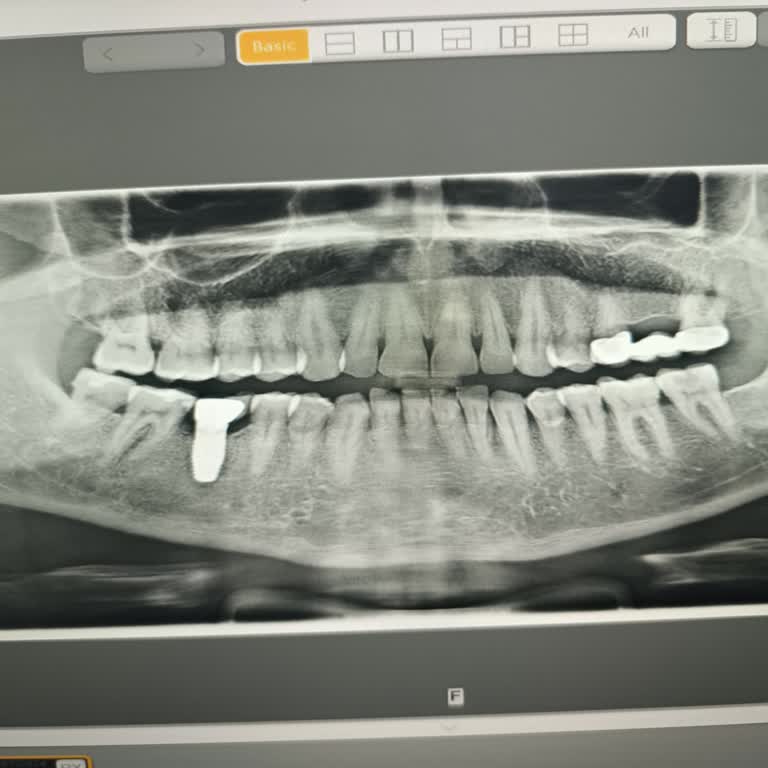

2022 Ocak ayında İstanbul Bağcılar Erkut Ağız ve Diş Sağlığı Merkezi’nde E***** E*** tarafından gerçekleştirilen implant işlemi sırasında, işlem öncesi ve sonrası röntgen çekilmeden uygulama yapıldı. Bu nedenle implant yanlış yerleştirildi ve sinir hasarı oluştu. İşlem için IBAN üzerinden 4.000 TL ö...